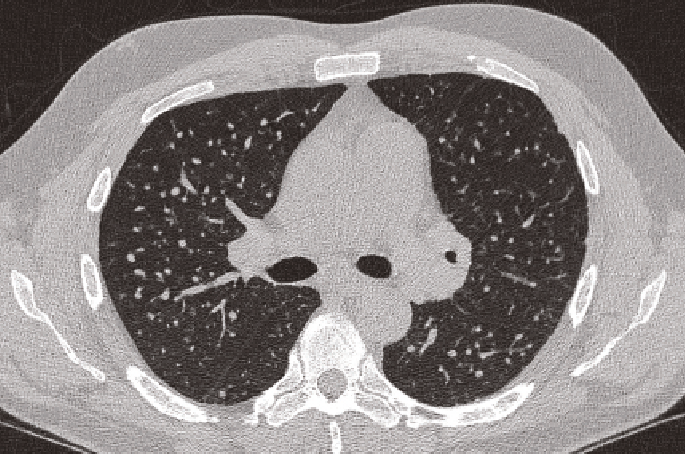

En ese sentido, todo proceso industrial debe poseer en su respectiva área, la mejor ventilación posible, porque los operarios e ingenieros de planta, son los más expuestos a todo tipo de toxinas, incluidos los polvos de sílice cristalina, la causante de afecciones pulmonares, y aunque, los macrófagos son las células que intentarán protegernos de tales intrusiones en los tejidos, cuando no lo logran, simplemente se formarán nódulos fibróticos en los pulmones, dificultando la respiración de manera paulatina y creciente, por el aumento de las cicatrices debido a la constante exposición.